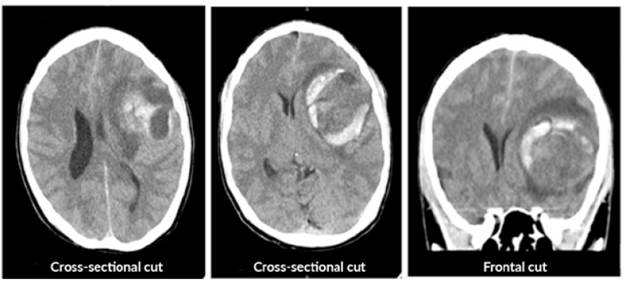

The patient was assessed by neurology, which requested a simple computed axial tomography (CT) of the brain, whose report suggested spontaneous intracerebral hemorrhage, described as a temporary lesion that displaces the midline and is accompanied by bleeding and perilesional edema (Figure 1). Various differential diagnoses were proposed, including brain tumor, glioblastoma, astrocytoma and middle cerebral artery aneurysm.

An emergency craniotomy for drainage was scheduled based on the results of the CT scan. Craniotomy showed a yellowish, hard tumor mass with necrosis and suggestive of astrocytoma. The patient did not require antibiotic management after the procedure and a new CT scan was requested, which showed satisfactory tumor resection with residual perilesional edema, without deviation from the midline (Figure 2). The histopathological study described resection compatible with glioblastoma (Figure 3).